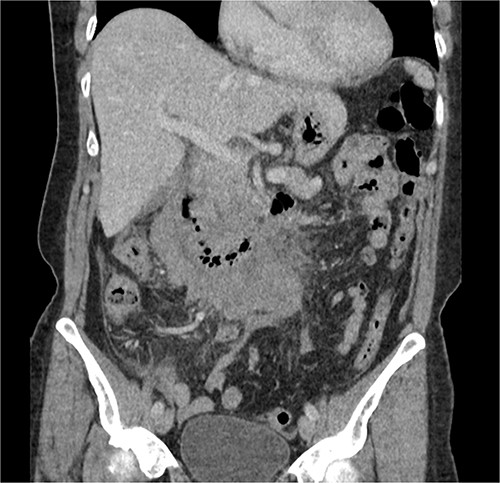

The radiologist suggested a computer tomography (CT) scan to further explore the potential causes for this fluid. The CT abdomen and pelvis revealed extensive oedema and induration surrounding the duodenum with a complex hyperdense fluid, extending from this site to the paracolic gutters and into the pelvis. While these findings are suspicious of a paraduodenal hemorrhage from a ruptured duodenal ulcer and hemoperitoneum, they were not typical for perforated duodenal ulcer or erosion into the blood vessels. Differentials were an infiltrating mass either fibrotic or of a lymphoproliferative origin. However, this could not explain the complex fluid in the abdomen (Figs 1 and 2).

CT abdomen, coronal view. Hyperdense fluid centered around the duodenum and tracking into the paracolic gutters. Appearance concerning for paraduodenal hemorrhage, infiltrating mass was considered less likely.